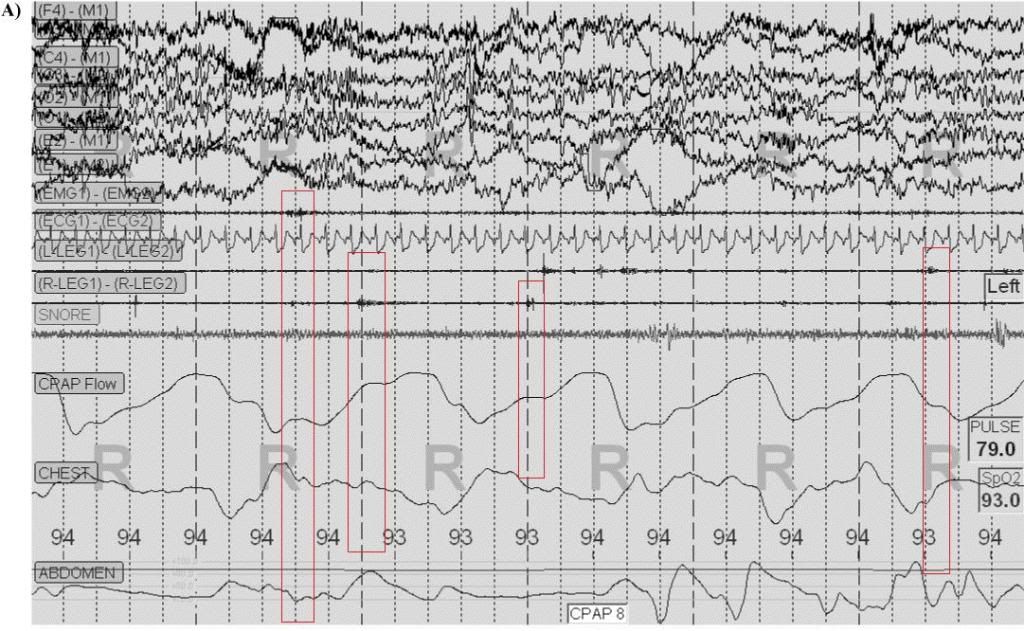

Unfortunately, it isn't "ballistocardiographic effect" this time, as much of the "expiratory intolerance" appears to be related to body motion (see movement in chin and leg leads):mollete wrote:Presently, his scheme is to use ASV. He's still touting "Expiratory Intolerance", but sheepishly says "Yeah, well could be ballistocardiographic effect", a concept he was also introduced to here.

Further, that really doesn't look a lot like REM ("R"), looks more like NREM2. Or else that chin movement makes this REM Behavior Disorder. Chest belt inverted (backwards). Abdominal belt looks blown.